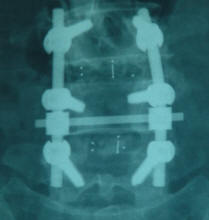

29-JULY-2012  YUSRA SALAMEH AL-JAMAEEN  55 YEARS  SPONDYLOLISTHESIS L3-4 AND EXTRUDED DISC L4-5 WITH LEFT FORAMINAL OCCLUSION AND SEVERE LUMBAR CANAL STENOSIS BOTH LEVELS.

Laminectomy of L4 and upper half of L5 and lower 2/3 of L3 with foraminotomy L4, L5 roots both sides. The extruded disc L4-5 was approached from the left side and discectomy of L4-5 was done. Discectomy of L3-4 was also performed and insertion of TLIF cages 9x10x28 mm was achieved to both levels with bone graft. Using Scientex IsoBar TTL system with polyaxial screws 6.2x45 inserted to L5 and L3 bodies and monoaxial same dimensions to L4 body. Rods bended to accept the natural curve of the spine 5.5 mm thickness with cross connector were used to fuse L3,4 and L5 bodies. ISIS stimulation was used and the roots were responding to 2-4 mA DNS, but the screws were not responding even to 15 mA.  Bone graft was aided lateral to the rods.